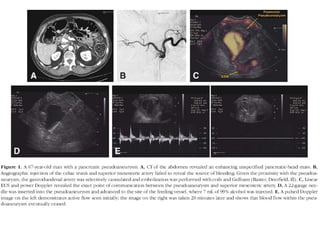

Pancreatic Pseudocyst